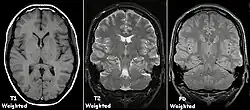

Je nach Gewichtung kommen die verschiedenen Gewebe in charakteristischer Intensitätsverteilung zur Darstellung:

- In der T1-Wichtung (T1w) erscheint Fettgewebe hyperintens (signalreich, hell) und damit auch fetthaltige/-reiche Gewebe (z. B. Knochenmark). Diese Gewichtung eignet sich daher gut zur anatomischen Darstellung von Organstrukturen und insbesondere nach Kontrastmittelgabe (Gadolinium) zur besseren Abgrenzbarkeit unbekannter Strukturen (z. B. Tumor).

- In der T2-Wichtung (T2w) erscheinen stationäre Flüssigkeiten hyperintens, so dass flüssigkeitsgefüllte Strukturen (z. B. Liquorräume) signalreich und damit hell erscheinen. Dadurch eignet sich diese Gewichtung zur Darstellung von Ergussbildungen und Ödemen sowie z. B. zur Abgrenzung von Zysten gegenüber soliden Tumoren.

- Protonendichte-gewichtete (PDw) Bilder sind flau (weniger Gewebekontrast), aber scharf. Knorpel kann sehr detailliert beurteilt werden. In Verbindung mit einem Fettsättigungsimpuls gehören PDw-Bilder deshalb zum Standard in Gelenkuntersuchungen.